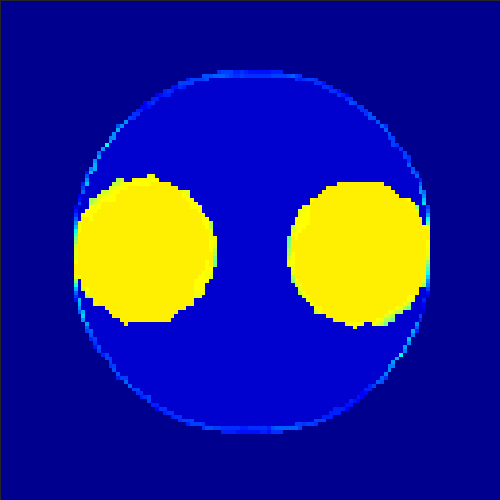

5.2 Monte Carlo Simulation

In order to test the behaviour of the proposed method in a more realistic, random-based test case, we performed a Monte Carlo simulation for dynamic SPECT imaging. First, we created a simple image phantom consisting of an outer and two inner circles which represents the structure of the region of interest (see figure 8(a)). Within those regions we assumed concentration curves over a time period of 90 time steps as displayed in figure 8(b). Based on the tracer intensity in an image frame at each time step, we created a variable number of random decay events (where the number is proportional to the average concentration in one pixel in the whole image frame per time step) with a probability proportional to the concentration in every subregion. They are detected by a virtual double head gamma camera rotating around the patient by 46 degrees per time step, which consists of 374 detector bins. Every simulated decay event is projected onto the scanner and counted by the corresponding detector bin.

In two different tests we fixed the number of events counted by the detector equal to (resp. ) times the average concentration in one pixel. The resulting sinogram images of the accumulated counts in each bin are shown in figure 9.

Based on the sinogram data we applied the proposed algorithm in order to reconstruct the original image sequence. The results for both test cases are shown in figure 10.

As one can see, the method is able to reconstruct the regions properly, even in case of a low count number. Within a number of iterations (average of 100 outer and 10000 inner iterations), the algorithm presents a reasonable reconstruction of the region of interest and the corresponding regional tracer concentration curves. Here, the parameters were not optimized as in the case of the synthesized data sets in the previous section, but kept fixed as , and . With futher optimized parameter values one could possibly provide even better results.